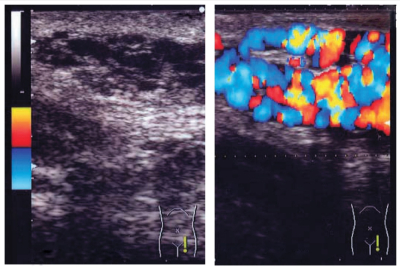

立位での左陰囊上部の写真を別に示す。破線で囲まれた部位に腫瘤を触知する。腫瘤は柔らかく、仰臥位で縮小し立位で腹圧を加えると腫大する。臥位での破線部の安静時超音波像と腹圧時カラードプラ超音波像とを別に示す。